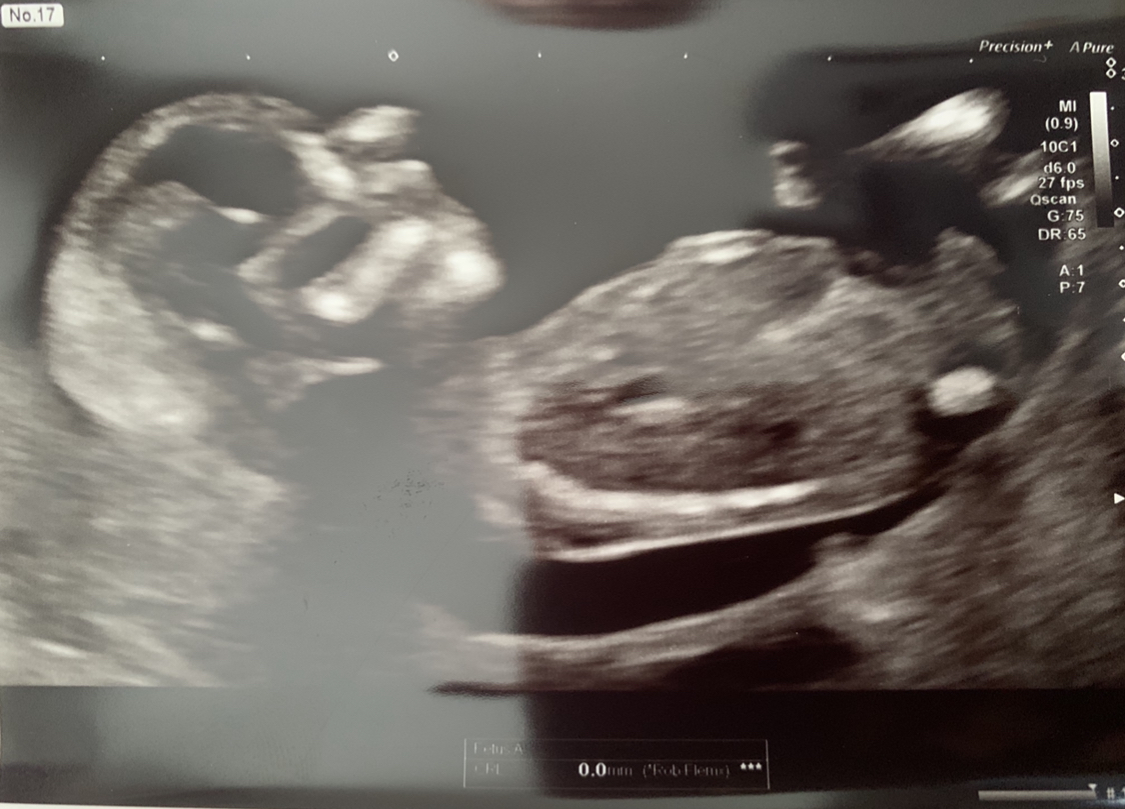

Hey, any guesses boy or girl? 12 weeks 6 days here

Tentative pink lean based on the top pic. In the bottom one I'm not sure what I'm seeing, I feel the nub is not captured and the second picture looks boyish, but that nub in the top one may just not be on the second shot

Boy guess from me. Think There’s stacking on the first photo and the second looks boyish too. Hope you get what you hope for if you have a preference :)

We had our gender scan today and it’s a girl 🥰